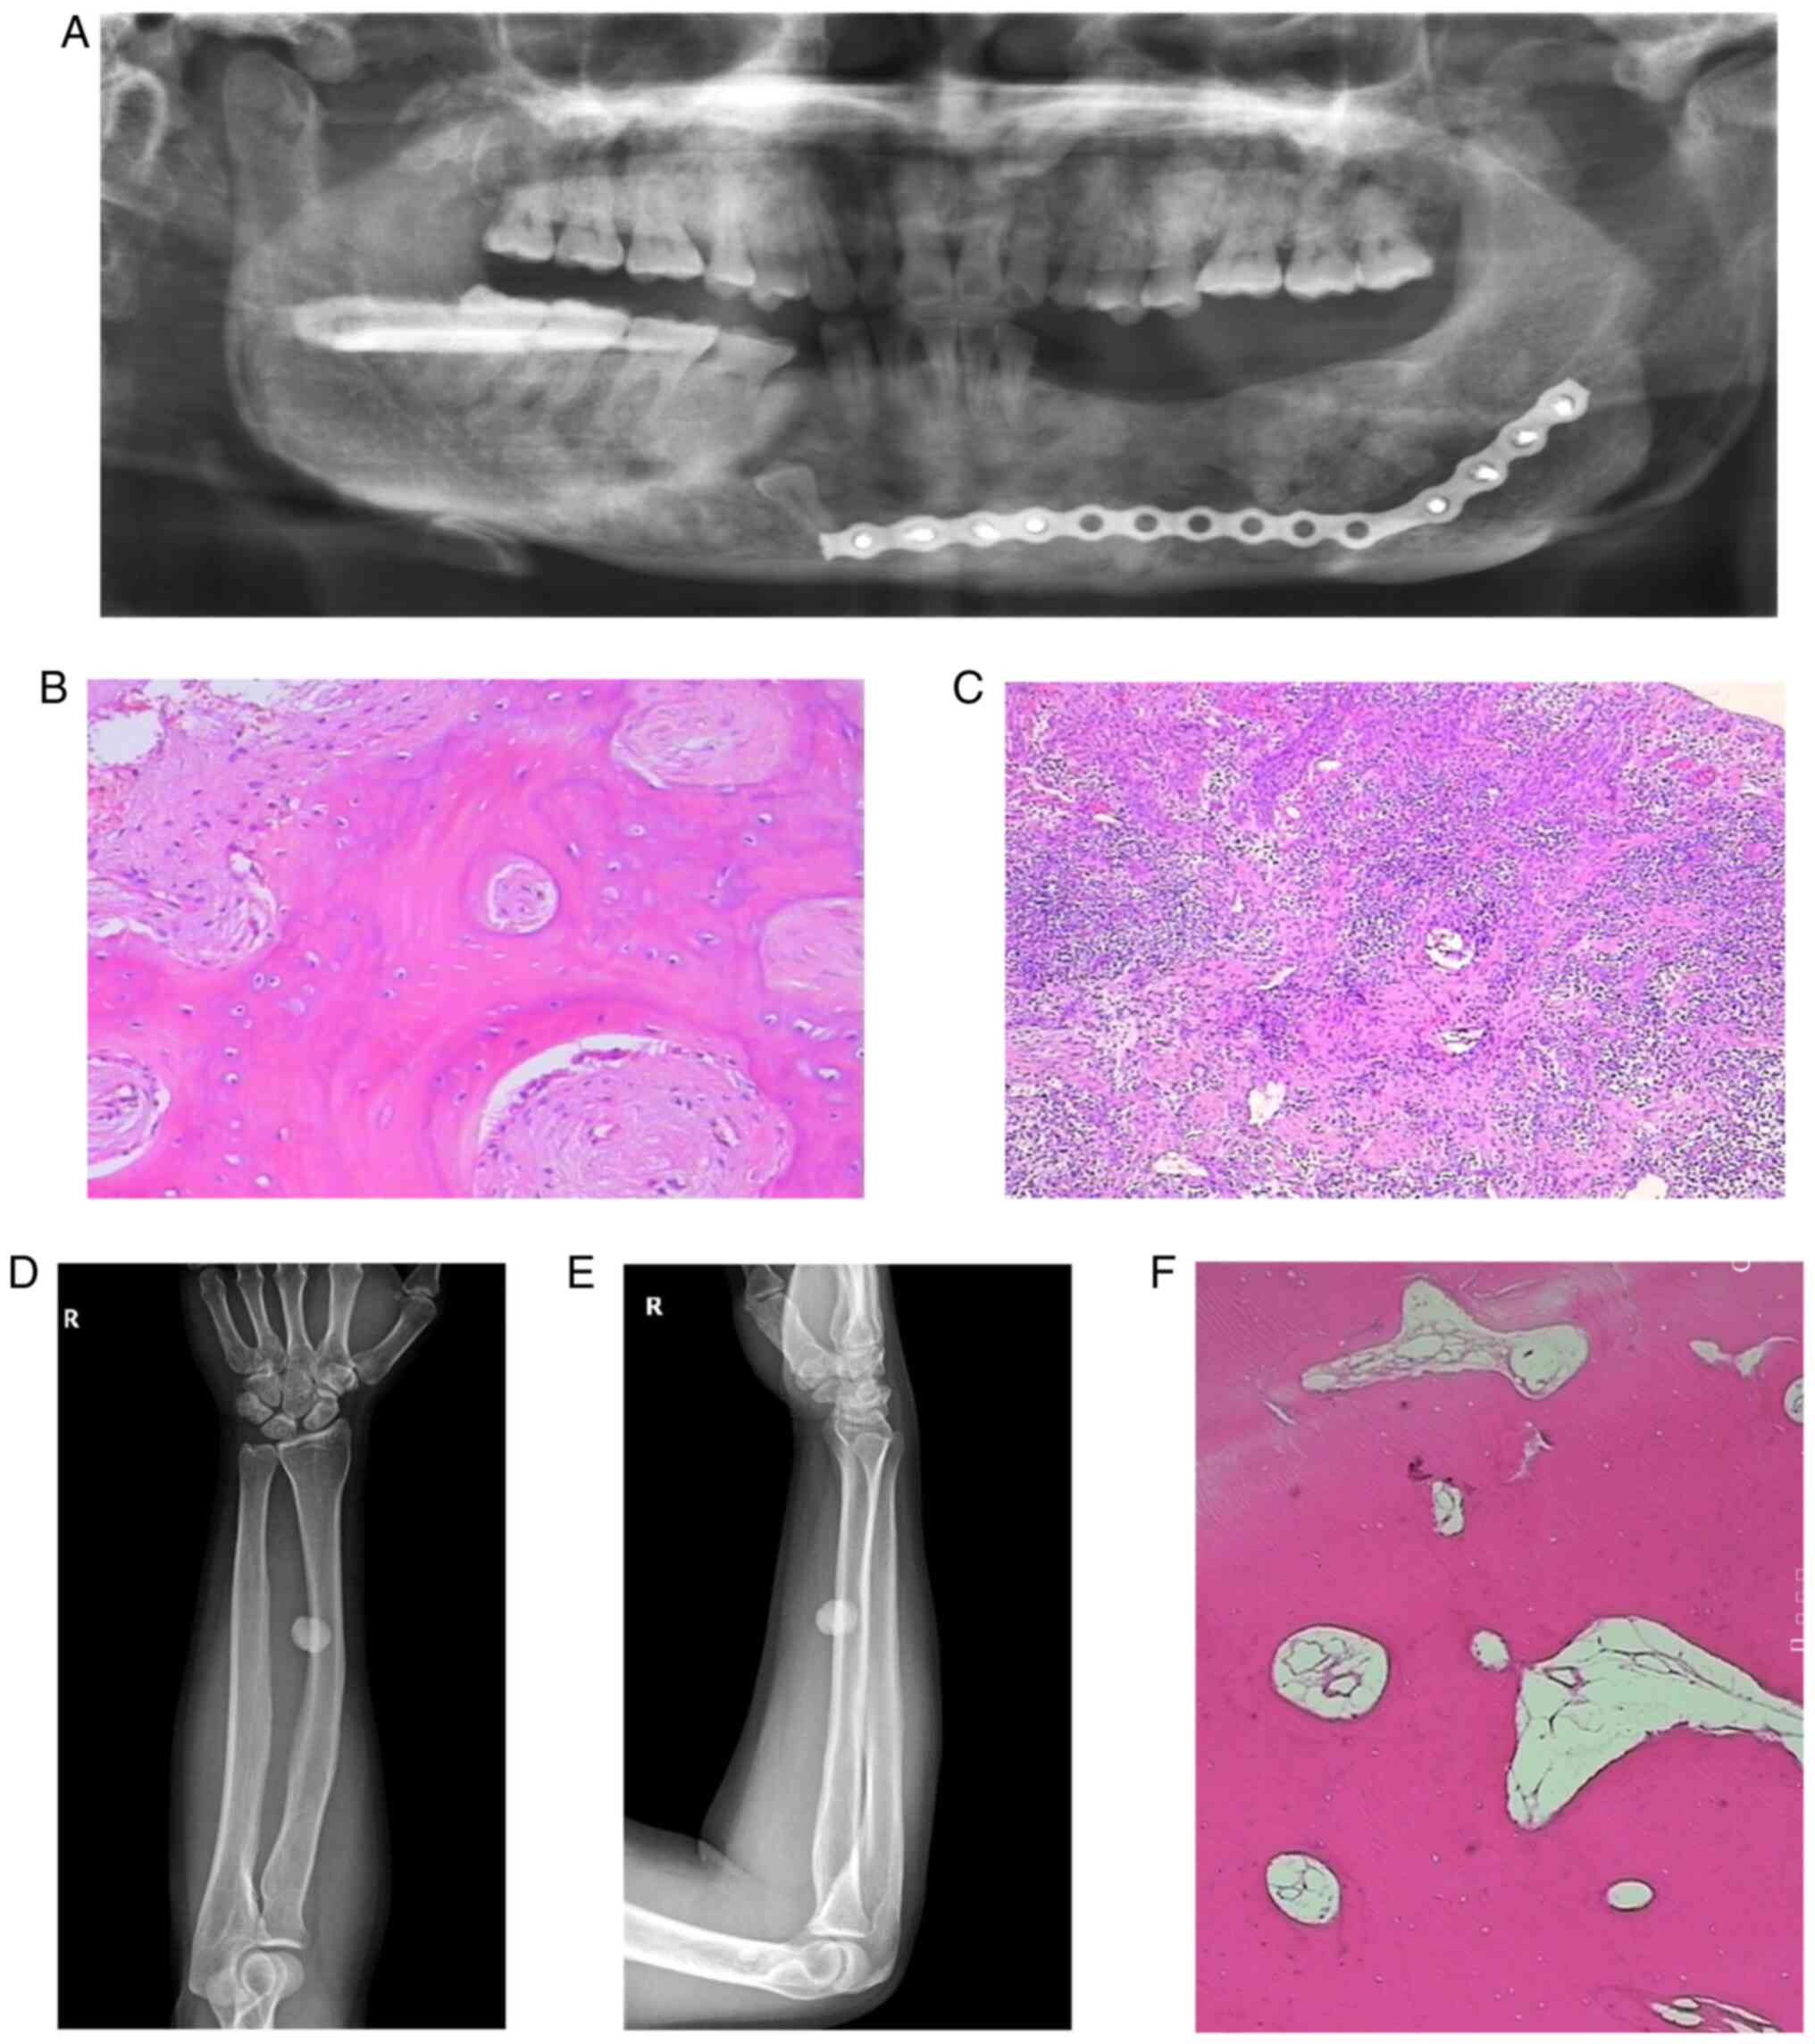

The postoperative X-ray dental panorama (Fig. 1A) of the proband showed that there were impacted teeth in the right lower jaw, and that most of the left mandibular teeth were absent. Regions of dense radiopacity were observed around the teeth. Radiological reporting of these scans confirmed the dense radio opacities to be consistent with the presence of osteomas.

Figure 1

(A) Postoperative oral X-ray, panoramic film. (B and C) Pathological sections on hyperosteogeny tissues of the left and right mandibular bone (magnification, x400 and x100, respectively). (D) The radius and ulna of right forearm on anteroposterior radiograph. (E) The radius and ulna of right forearm on lateral radiograph. (F) Pathological sections on hyperosteogeny tissue of the right tibial (magnification, x400).

Pathological sections were obtained from gray-brown bone tissue of the left and right mandible (Fig. 1B and C). The results confirmed that the mandibular osteoma tissue consisted of a well-differentiated lamellar bone. The trabeculae were connected with each other with scattered, loose connective tissue was indicated between them. There was no obvious abnormal shape in the bone cells with osteoblasts being visible. A large number of acute and chronic inflammatory cells had localized to the site of injury. The left mandibular alveolar had lesioned with hyperplastic spindle cells growing with a spiral shape in this area. The trabeculae in this region were curved, and osteoblasts were visible around them. Osteoblasts showed no obvious abnormalities.

The radius and ulna of the right forearm on anteroposterior and lateral radiographs (Fig. 1D and E) revealed the presence of a circular high density shadow. The boundary of the shadow was clear with an approximate size of 1.7 by 1.5 cm. The shape and density of the ulna and tibia were normal. No definite hyperosteogeny or destruction was indicated. No fracture line was observed and the soft tissue was normal.

Pathological sections were obtained from hyperosteogeny tissue of the right tibial (Fig. 1F). The results confirmed that the tissue consisted of a well-differentiated lamellar bone, and that the cells were not abnormal. These results were consistent with a diagnosis of osteoma.